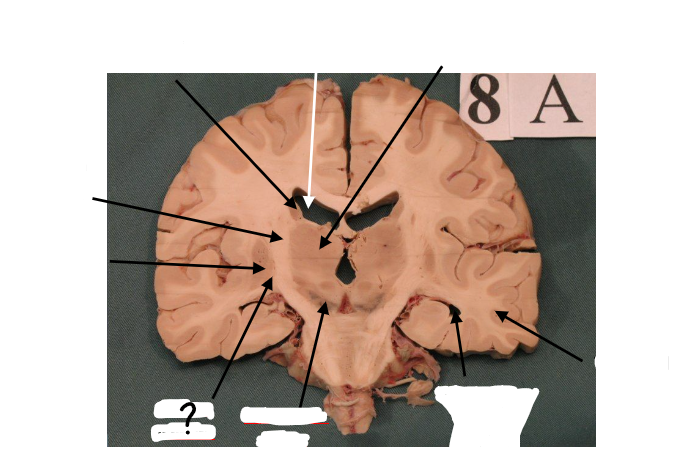

body of caudate nucleus

lateral ventricle

thalamus

internal capsule

putamen

globus pallidus

substantia nigra

inferior horn of lateral ventricle

temporal lobe

gp external and gp internal